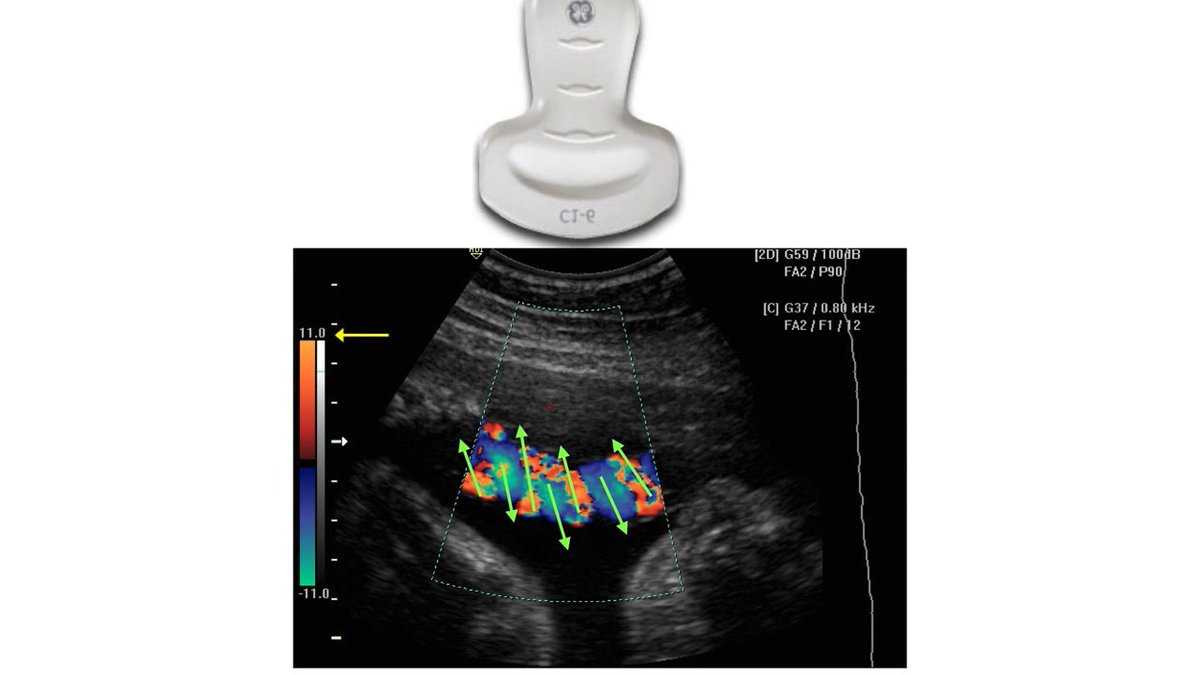

في " الـ convex probe ”

اذا فتحنا الـ box يكون البروب فوق دائماً .

طيب لو فرضنا ان الـ box مو موجود نعرف مكان البروب عن طريق

" simple volume and angel cursor “ نرسم خطين تخيلين ( الخط الي يلمس الـ beam path من "الجهه العلويه " راح يكون البروب بنفس الجهه هذي )

مثال : لو الخط الي رسمناه لامس الـ beam path من اليمين راح يكون البروب يمين والعكس

طبق المعايير الي فوق على هالصورتين وبتعرف هل الاتجاه صحيح او لا